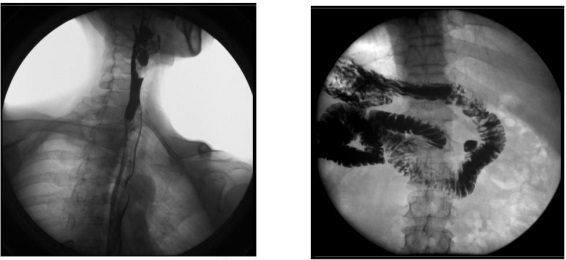

2、數字化胃腸功能:適用于胃腸道造影檢查,如食管造影、上消化道造影、全消化道造影等。

2) 肛腸科:可應用氣鋇雙重造影和排便造影(DFG)功能,可檢查大腸的細小病變,如小息肉、早期腫瘤、潰瘍等效果良好;可檢查肛管炎、恥骨直腸肌綜合癥、骶骨部畸胎瘤、直腸前突、直腸內套疊、肛門直腸損傷和異物等檢查。

3、其他造影:適用于各種普通及特殊造影,如口服膽囊造影、靜脈膽道造影、T 管造影、逆行胰膽管造影(ERCP)、靜脈腎盂造影(IVP)、子宮輸卵管造影等。

2) 肝膽外科:膽管手術后,切開膽總管植入 T 管引流,起支撐作用,防止術后膽總管狹窄,術后應用胃腸機進行膽管造影(T 管造影),檢查膽道內有無殘留結石及異物,是否通暢無阻, 對手術進行評估;